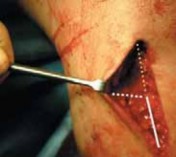

INITIAL DISSECTION

1. Proper bony anatomic landmarks are located.

1. The tibial tubercle, posteromedial tibia, and joint line are clearly identified with a skin marker.

2. The incision lies 2 to 3 cm posterior to the tibial tubercle and 1 cm distal to the joint line, and extends distally for 5 to 6 cm (

TECH FIG 2A

).

2. The incision is taken down through the skin and subcutaneous tissues, revealing the sartorius fascia (

TECH FIG 2B

1. The superior border of the gracilis hamstring tendon is palpated, and the sartorius fascia is opened along the superior border of the gracilis tendon.

2. Medially, the pes bursa is released from the medial tibial tubercle in an inverted L fashion.

3. The pes bursa is carefully elevated distally, taking great care to develop the plane between the bursa and the underlying medial collateral ligament.

4. Proximally, the retinaculum and layer 1 of the knee are incised to the approximate level of the joint line (

TECH FIG 2C

3. Anteriorly, the patellar tendon is identified, and a plane posterior to the tendon is identified. A Z-retractor is placed under the tendon to protect it.

1. Occasionally, the most superior fibers of the patellar tendon attachment to the tibial tubercle must be elevated to avoid inadvertent creation of the osteotomy through the patellar tendon.

4. Posteriorly, the MCL is dissected subperiosteally using a Cobb elevator, which is taken back toward the posteromedial border of the tibia.

1. The Cobb elevator is then used to dissect the muscles and tissues from the posterior tibia along the line of the osteotomy. Care must be taken to stay directly on the posterior tibial bone to avoid neurovascular injury.

2. After adequate posterior dissection, it should be possible to pass a finger bluntly across the posterior tibia. For further protection of the posterior neurovascular structures, a laparotomy sponge is placed across the back of the knee.

3. Finally, another Z-retractor is placed posteriorly to retract the pes bursa, MCL, and posterior neurovascular structures (

TECH FIG 2D,E

TECH FIG 2 • A. View of the anteromedial knee showing the proper bony landmarks. PMT, posteromedial tibial border; TT, tibial tubercle; arrowhead, joint line;

, level of hamstring tendons. B–E. Dissection from an anteromedial view. B. Overall orientation of incision through subcutaneous fat, down to sartorius fascia. C. Close-up of incision. The sartorius fascia is opened just superior to the gracilis tendon, and the pes bursa is elevated off in an L-type fashion. An incision also is made proximally in the retinaculum. D. This incision reveals the fibers of the medial collateral ligament (MCL), which are then dissected subperiosteally with a Cobb elevator. E. Retractors are placed under the patellar tendon and at the posteromedial tibia. #### PLACING GUIDE PINS